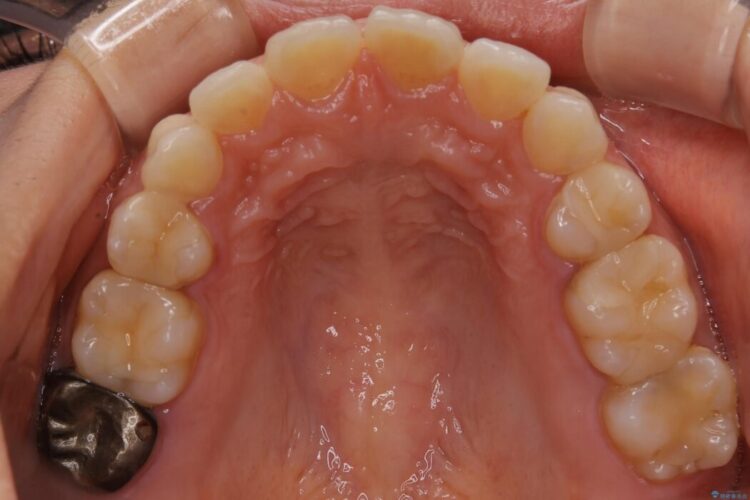

抜歯矯正後の後戻りについてご相談にいらした患者様です、

後戻りの程度としては軽度なので、治療期間としては短く終えることが出来ました。

前歯の正中線も改善され大変満足していただきました。